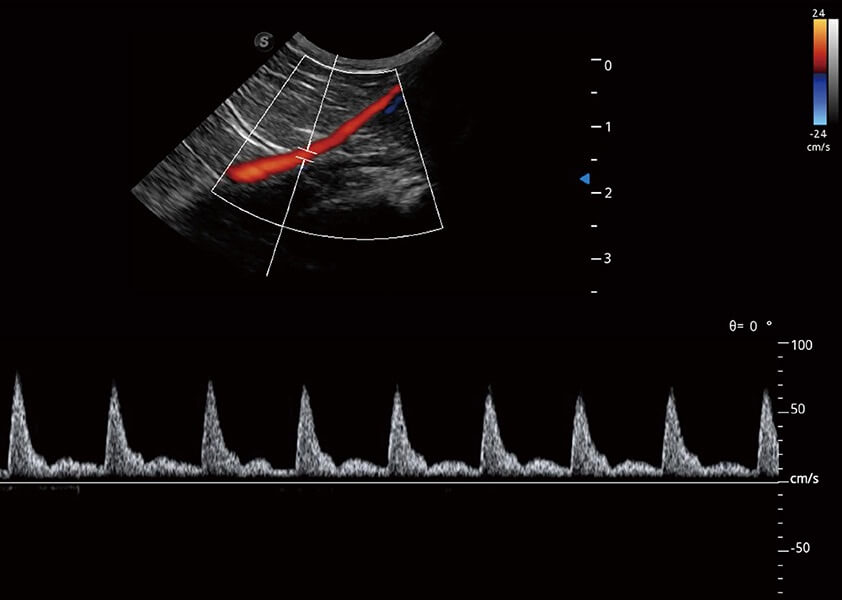

ProPet 60 作为一款高端台式动物超声设备,为动物医生的日常诊断提供了一系列贴合动物临床需求、解决临床实际问题的高级成像功能。凭借全系列高清探头,满足医生对腹部、心脏、生殖、浅表、肌骨等成像的所有需求,切实帮助您提升检查效率,提高诊断信心。

兽用彩色多普勒超声诊断系统